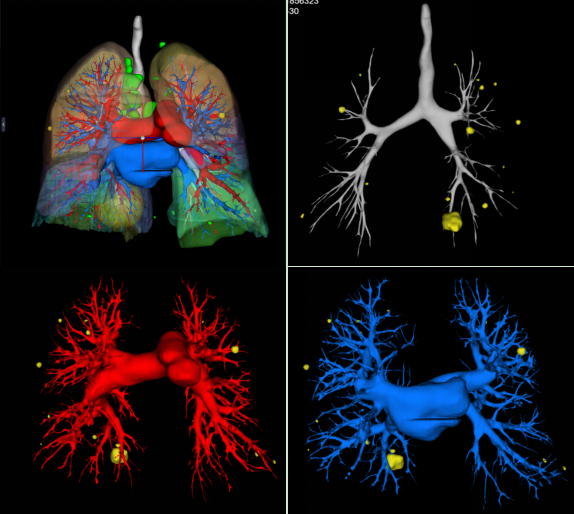

(三)肺結(jié)節(jié)三維可視化重建CT檢查,可結(jié)合原始軸位圖像清晰顯示肺結(jié)節(jié)與周圍毗鄰關(guān)系,尤其是與周圍動靜脈血管的解剖關(guān)系,指導(dǎo)臨床手術(shù)方式的抉擇。

圖片

肺結(jié)節(jié)三維可視化重建CT檢查